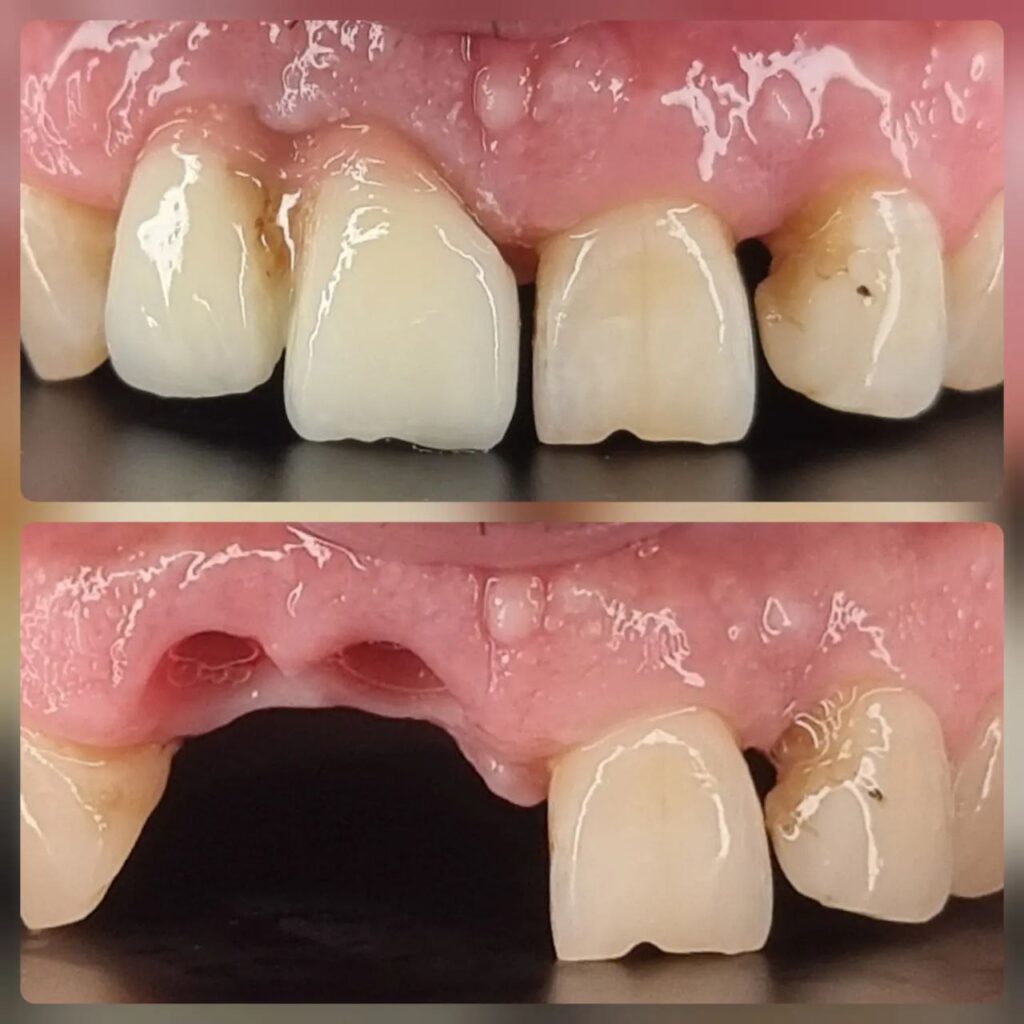

کاشت ایمپلنت دندان

اطمینان حاصل کردن از اینکه دندانهایتان به نحوی زیبا و طبیعی جایگزین شدهاند، از اهمیت بسیاری برخوردار است. ایمپلنت دندان به عنوان یک روش درمانی دائمی در دندانپزشکی شناخته میشود که حاصل آن، یک دندان زیبا و طبیعی در دهان شما خواهد بود.

هرچند که این روش درمانی هزینهی بیشتری نسبت به روشهای دیگر دارد، اما ارزش زیبایی که ایجاد میکند، قابل انکار نیست. ایمپلنتها به قدری شبیه به دندانهای طبیعی هستند که به سختی میتوان آنها را از دیگر دندانها تشخیص داد.